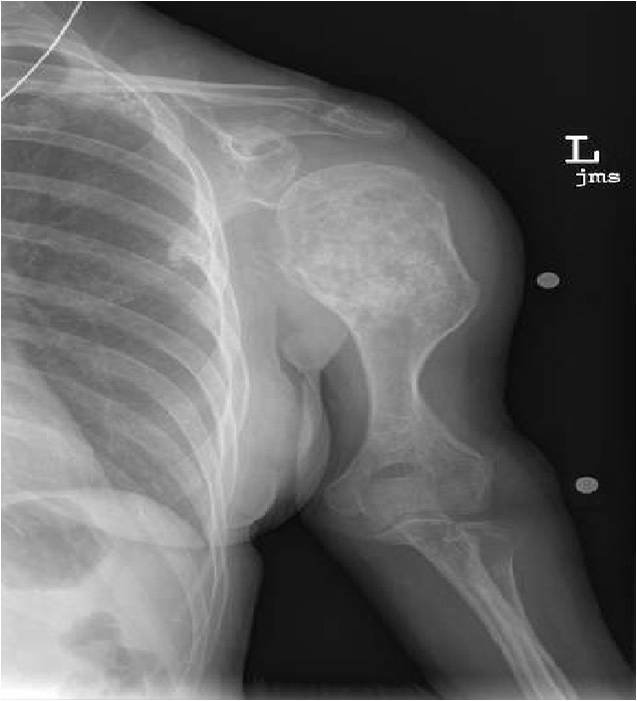

- Proximal Humerus, Femur most common long bones

- Localized, radiolucent defect usually with punctate calcifications

- Calcifications are typical but not always present

- Matrix may demonstrate various degrees of calcification

- Calcifications are stippled, punctate, popcorn like calcifications and “Ring and Arc” calcifications

- Cartilage tumors grow in a lobular manner. The perimeters of the lobules undergo

- enchondral ossification that may calcify. If the entire perimeter of the lobule calcifies it appears

- radiographically as a “Ring”. If a portion of the perimeter of a lobule calcifies it forms an “Arc” on

- an X-ray.

- Geographic lytic lesion

- Central often metaphyseal in long bones

- Expansile remodeling with thinned cortex

- Chondroid matrix with calcifications in majority of tumors

- There should never be any cortical destruction nor a soft tissue component. If this exists then the tumor must be a chondrosarcoma.

- Endosteal scalloping and cortical expansion is acceptable for phalangeal tumors. In most benign long bone cartilage tumors there is minimal endosteal scalloping but there should be no cortical expansion nor thickening. There should be no cortical destruction and no soft tissue component associated with an enchondroma. Cortical destruction, periosteal thickening, cortical expansion and a soft tissue component indicates a chondrosarcoma of the long bone.